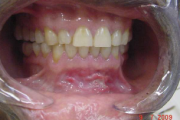

Aftoosne stomatiit